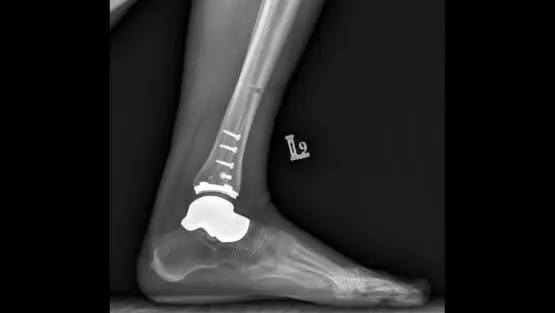

To technika obrazowania wykorzystująca promieniowanie rentgenowskie (promieniowanie X). Badanie rentgenowskie jest podstawową metodą obrazowania układu kostnego ze względu na szeroką dostępność, stosunkowo niskie koszty i krótki czas badania.

RTG, badanie rentgenowskie, zwane także potocznie prześwietleniem lub rentgenem, to technika obrazowania wykorzystująca promieniowanie rentgenowskie (promieniowanie X). Badanie rentgenowskie jest podstawową metodą obrazowania układu kostnego ze względu na szeroką dostępność, stosunkowo niskie koszty i krótki czas badania. RTG stosowane jest w medycynie już od ponad 100 lat, dzięki czemu jest to technika bardzo dobrze poznana i bezpieczna.

Na podstawie zdjęcia RTG ocenia się strukturę tkanki kostnej – np. ewentualne pęknięcia i złamania. U większości pacjentów z urazem kostnym dzięki badaniu rentgenowskiemu można zaplanować leczenie i kontrolować postępy gojenia. Rentgen nie nadaje się do oceny innych tkanek, czyli np. urazu więzadeł czy mięśni. Badanie RTG pokazuje jedynie zarys tkanek miękkich, a nie strukturę.